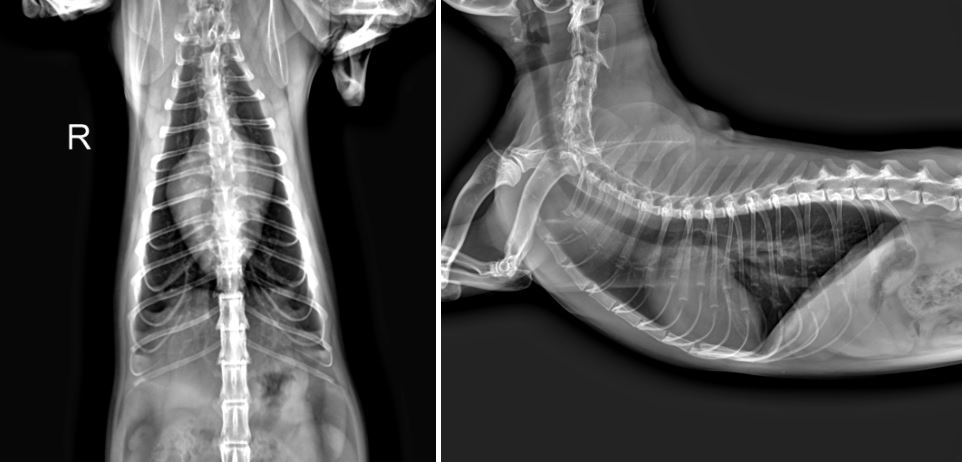

보리는 X-ray 상 현저한 심장 비대 및 좌심 확장과, 폐에 흉수가 차서 폐 부분이 하얗게 보이는 폐침윤이 확인되었습니다.

<X-ray 검사>